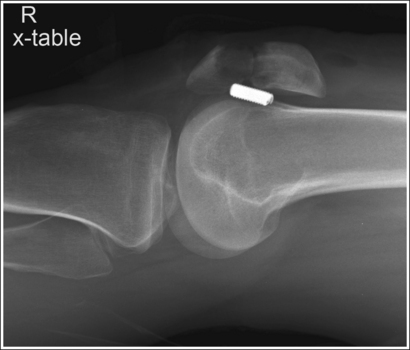

• Supine (cross-table) lateromedial knee projection. When a lateral knee projection is taken using a lateromedial projection, with a horizontal central ray, the cephalad central ray angulation described above is not required, as long as the patient's femoral inclination is not reduced or increased by the distal femur being shifted too laterally or medially, respectively. Images 70 and 71 are cross-table lateral knee projections that demonstrate a femoral condyle within the knee joint space because of poor femoral positioning. Image 70 demonstrates the lateral condyle in the joint space and image 71 demonstrates the medial condyle. When such images are produced, view how far the fibular head is positioned from the tibial plateau. When the distal surfaces of the femoral condyles are accurately superimposed, the fibular head will be positioned about 0.5 inch (1.25 cm) from the tibial plateau. If the central ray (CR) is rotated distally or the leg adducted (moved too medially) for a lateromedial projection of the knee, the lateral condyle will be projected distal to the medial condyle and the fibular head will move farther than 0.5 inch (1.25 cm) from the tibial plateau (see Image 70). If the CR is rotated proximally or the leg abducted (moved too laterally) for a lateromedial projection of the knee, the lateral condyle will be projected proximal to the medial condyle and the fibular head will move closer than 0.5 inch (1.25 cm) from the tibial plateau (see Image 71).